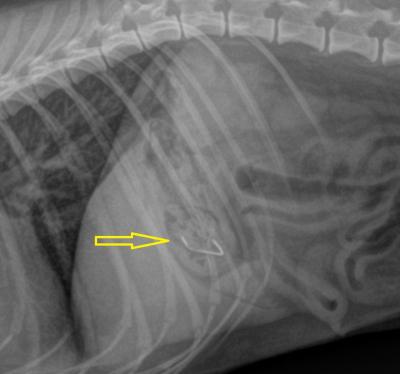

Tento kocourek zase asistoval při zabijačce. V jeho střevu můžete vidět kovovou svorku ve tvaru písmene "C".

Zde byla identifikace cizího tělesa snadná.